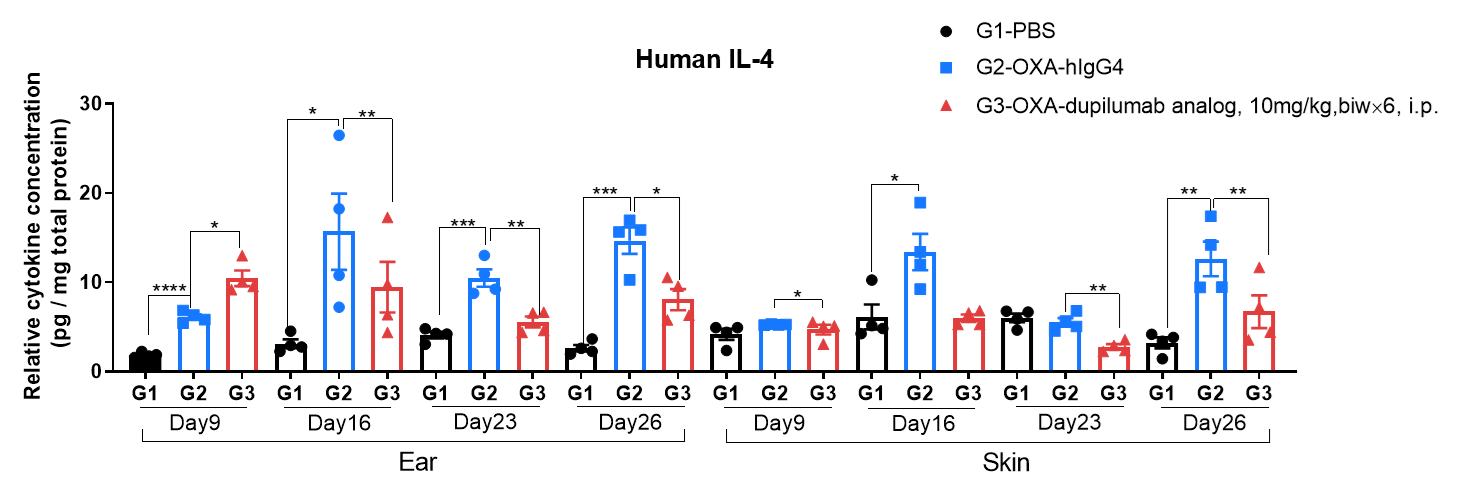

Protein expression analysis in OXA-induced AD model of B-hIL4/hIL4RA mice by ELISA.

Ear and skin samples of modeling area were collected from at day 9, 16, 23 and 26 and analyzed by ELISA. Tissue sample homogenate supernatants were loaded for ELISA detection, and the results were standardized by total protein concentration of the corresponding sample.